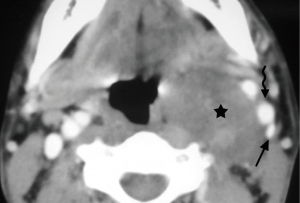

Schwannomas are benign tumors arising from Schwann cells surrounding peripheral nerves. Schwannomas in the carotid space most commonly stem from the vagus nerve. The tumor is usually a sharply demarcated round or oval mass with hypo-, iso-, or hyper-attenuation. Cystic degeneration, xanthomatous change, or areas of relative hypocellularity adjacent to densely cellular or collagenous regions usually contribute to heterogeneity of the tumor (Figure 1) (9,10). Schwannomas are hypovascular tumors, but in dynamic scans, they can show marked enhancement due to pooling of contrast agent resulting from poor venous drainage (11). More often, schwannomas demonstrate a variable degree of enhancement, most commonly patchy enhancement (Figures 2-7).

Due to its location between the vein and artery in the carotid space, schwannomas of the vagus nerve tend to separate the artery and vein, usually displacing the CCA/ICA medially and the IJV laterally (Figures 2,3) (12). Some schwannomas of the vagus nerve may displace the IJV and ICA/CCA in a posterior direction without splaying them and there is usually separation between the artery and vein (Figure 4). The cervical sympathetic chain runs in a fascial reflection posterior and slightly medial to the carotid space. Hence, schwannomas of the sympathetic chain tend to displace the IJV and CCA/ICA together, usually anteriorly and laterally (Figure 5) (5). A large schwannoma of the sympathetic chain may distort the surrounding anatomy and result in a posterior displacement of the carotid vessels without separation of the artery and vein (Figure 6) (13,14). Occasionally, a schwannoma of the cervical sympathetic chain may splay the internal and external carotid arteries at the carotid bifurcation but without encasing the arteries (Figure 7) (5). In these regards, the position of the tumor relating to the vessels in the carotid space is more important than the direction of vascular displacement. There has also been a reported case of schwannoma arising from the glossopharyngeal nerve in the carotid space causing posterior displacement of the ICA (15).